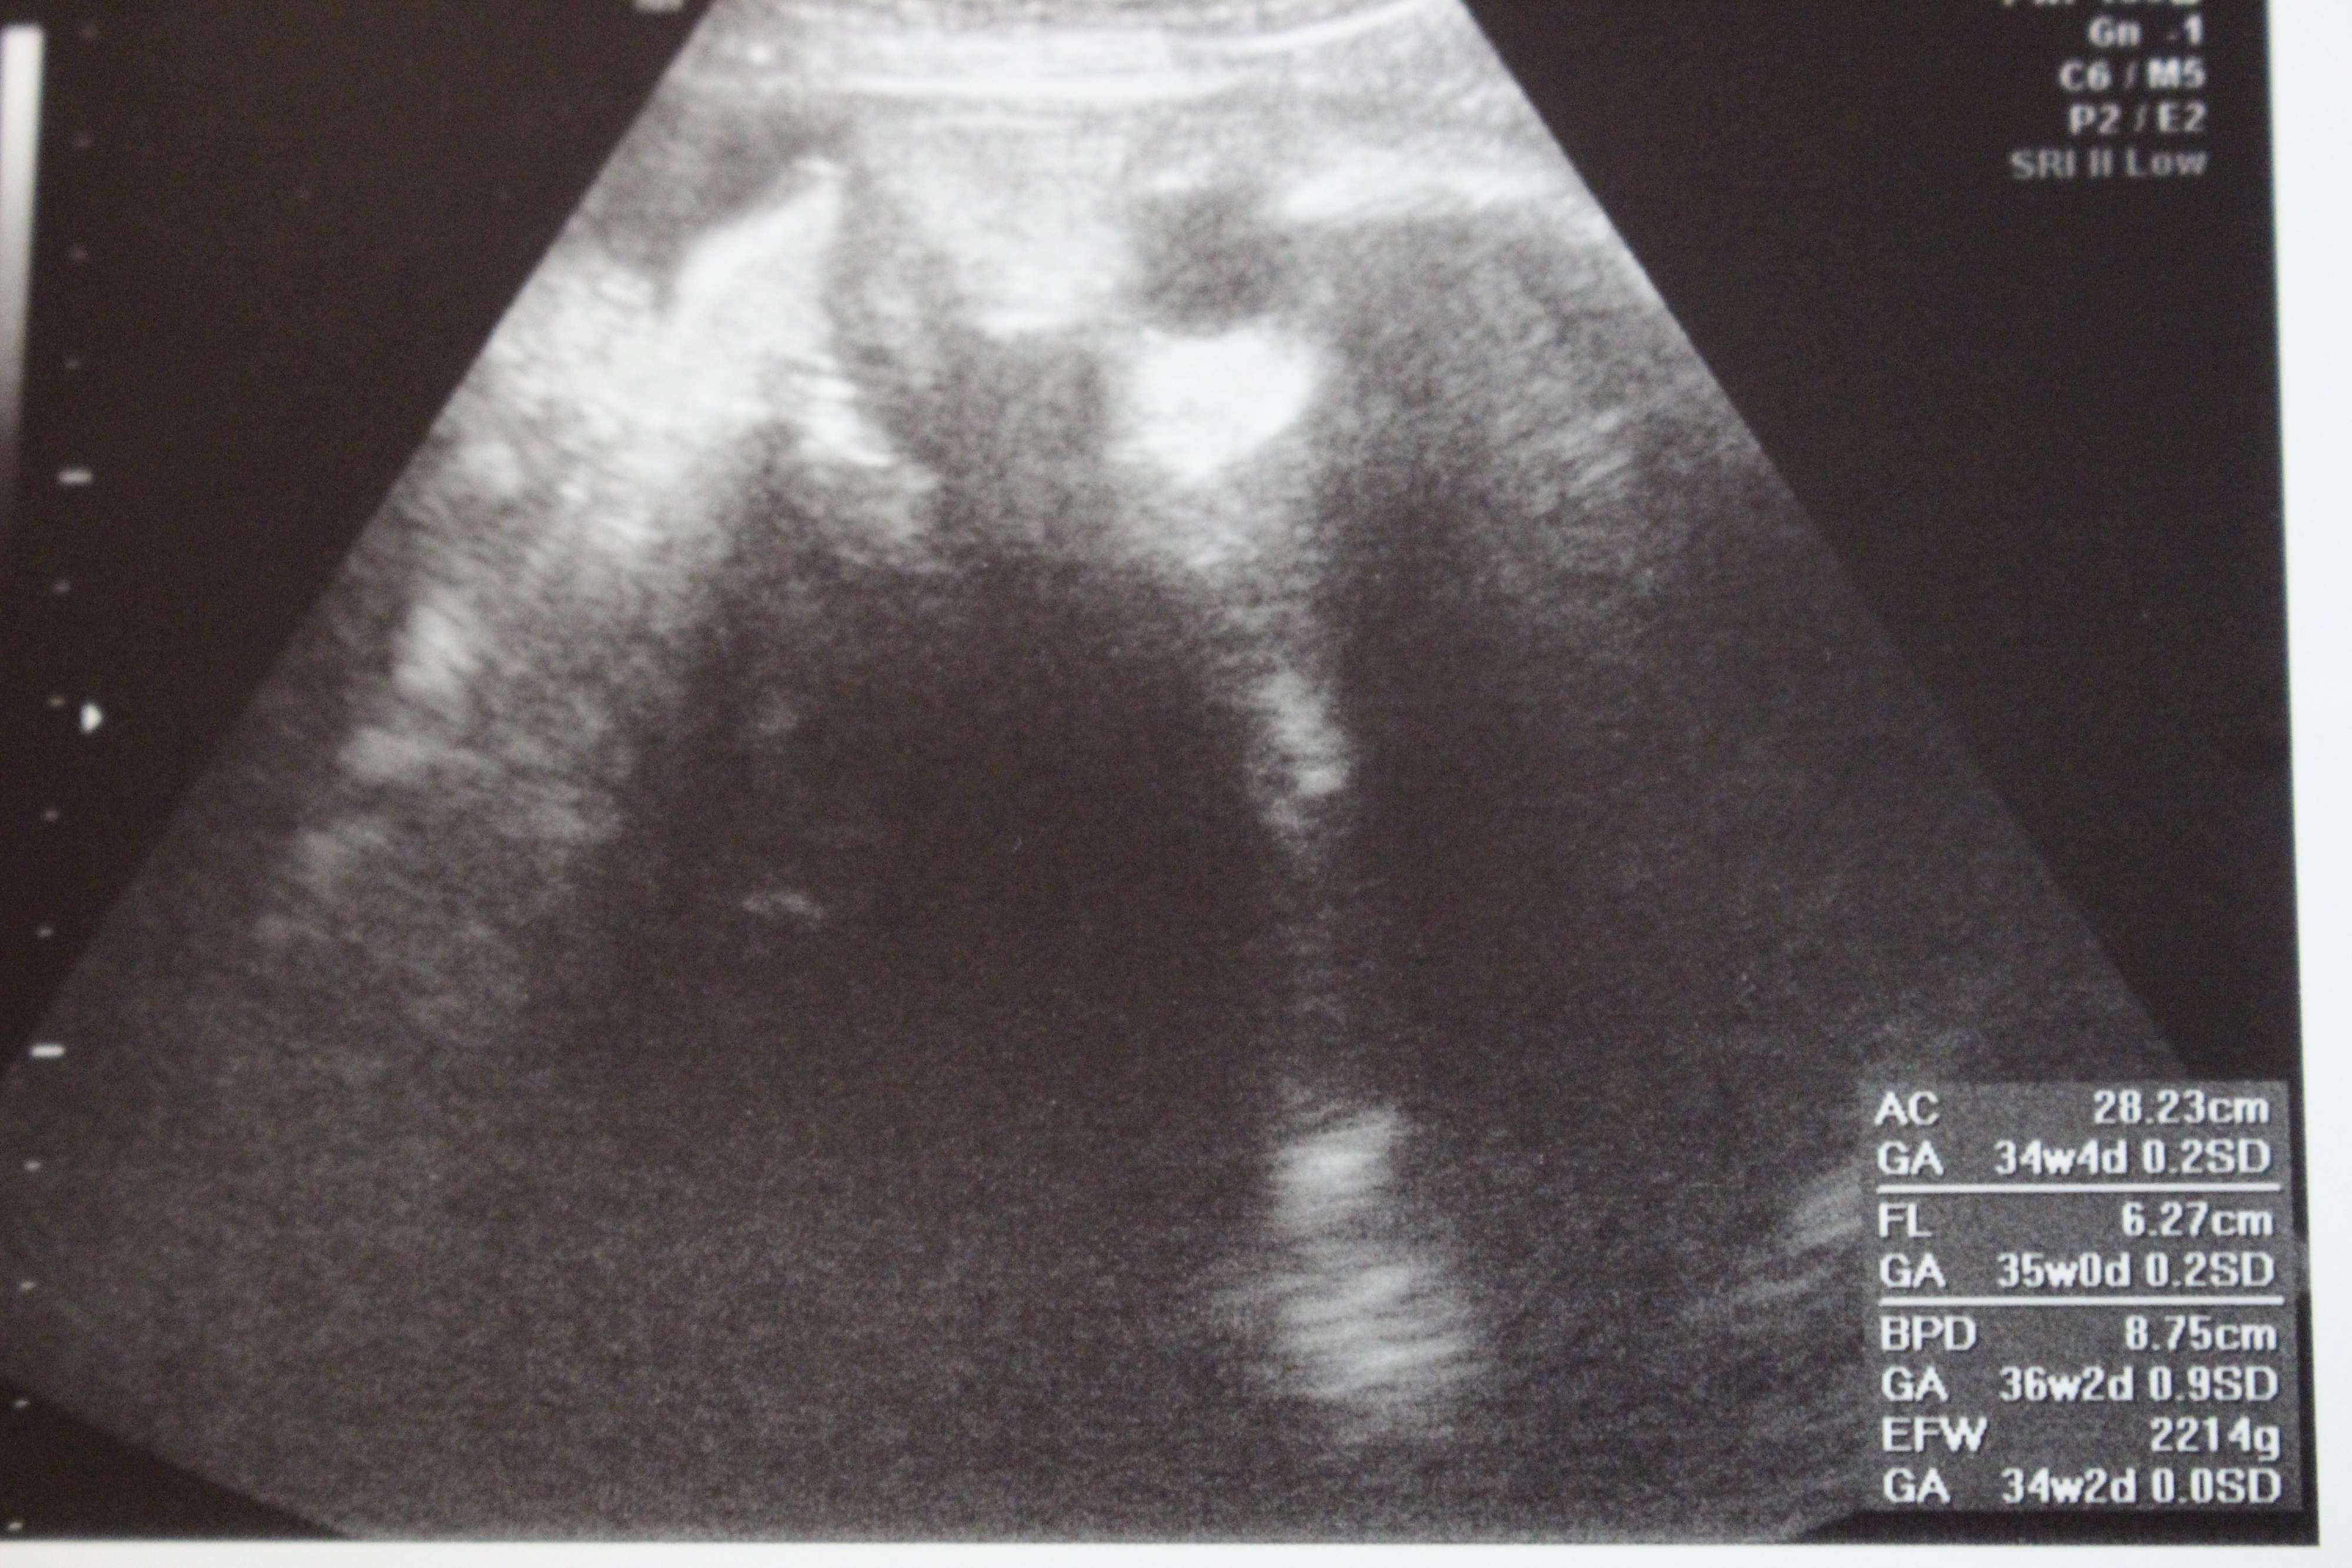

妊娠34週目のエコー写真

赤ちゃんの体重2214g。病院の食事はまずいと噂は聞いていたのですが、ご多分に漏れずこちらの産院も独特の味つけ。お見舞いに来てくれる友人・知人の差し入れがささやかな楽しみでした。